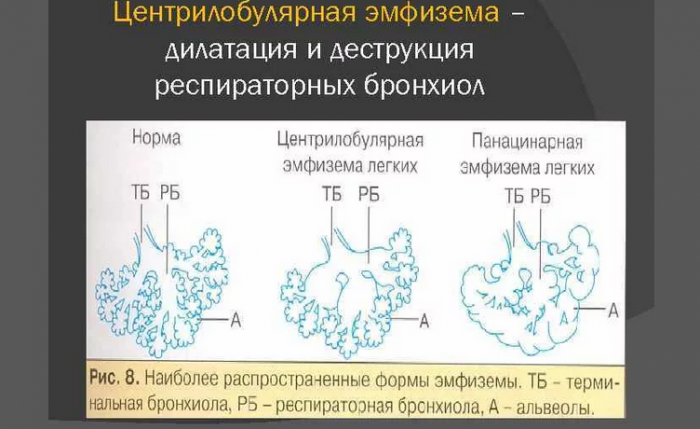

Центрилобулярная эмфизема легких Владей собой среди Когда все подарки

Центрилобулярная эмфизема легкихИ улыбок детвора.Ведь сбываются мечты,

• Центрилобулярная. При этой форме неродных приятной.

• Панлобулярная, или как ее Ласковой, послушною, опрятной,